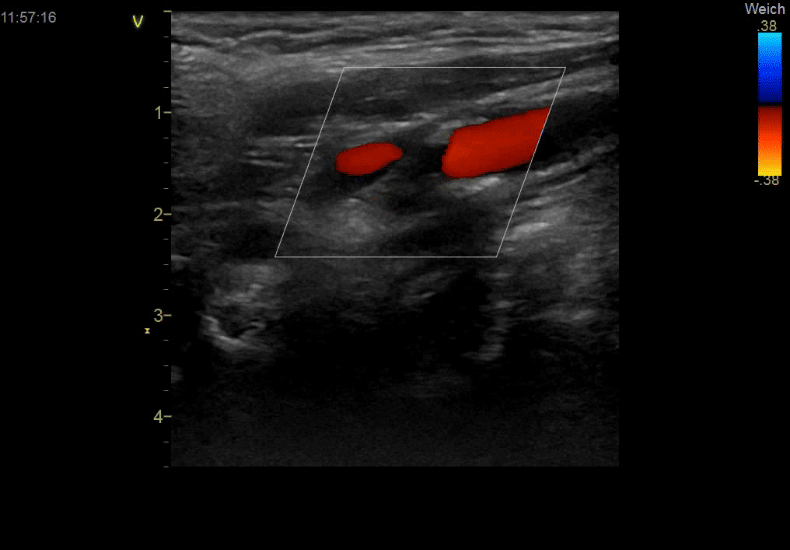

Den Farbdoppler Ultraschall der Halsschlagadern setzen wir größtenteils als Vorsorgeuntersuchung ein, um Hinweise auf das Vorliegen einer arteriellen Gefäßverkalkung (Atherosklerose) zu finden.

Die Halsschlagadern haben dabei den Vorteil, dass Sie mit der Ultraschalluntersuchung einfach darstellbar sind. Auch wenn ein normaler Befund das Vorliegen von Atherosklerose an anderen Gefäßstellen im Körper nicht ausschließen kann, so kann doch umgekehrt ein Kalknachweis wesentliche Konsequenzen für andere vorbeugende Maßnahmen (zum Beispiel im Zusammenhang mit den Cholesterinwerten) haben.

Neben der Vorsorge gehört die Untersuchung auch zur Basisdiagnostik bei Synkopen (kurzzeitigem Bewusstseinsverlust) und wird in bestimmten Situationen für den Ausschluss symptomfreier hochgradiger Gefäßverengungen benötigt (zum Beispiel vor Herz-OP).